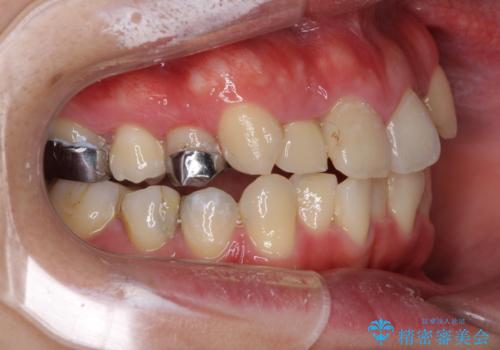

- 上下のデコボコと奥歯の咬みにくさを気にして来院された患者様です。

上顎骨の幅が下顎骨よりも小さいので、拡大装置により骨幅を広げて上下関係を改善し、その後インビザラインにて歯並びを整えることとしました。

上下の骨幅を改善したことで、スムーズに歯列矯正を行うことができました。

奥歯の咬み合わせを改善する必要があったため、治療は長期化しましたが、きっちりと仕上げることができました。